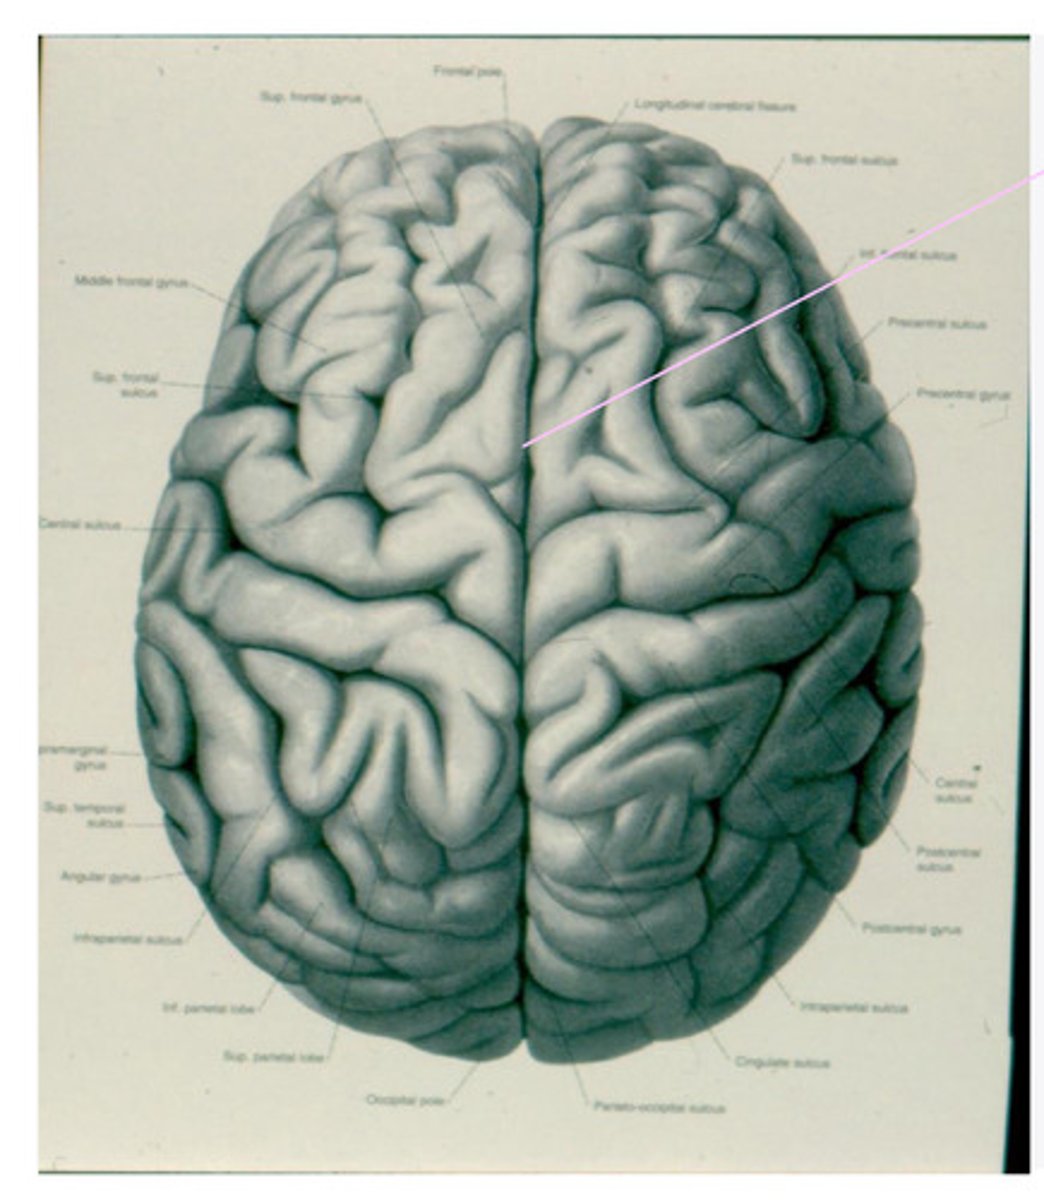

geri, sulci, lobes

What are the anatomical divisions of the cortex of the brain?

-frontal

-parietal

-temporal

-occipital

What are the 4 lobes of the brain?

central sulcus

What sulcus differentiates the frontal from the parietal lobe?

lateral sulcus

-precentral gyrus

-superior frontal gyrus

-middle frontal gyrus

-inferior frontal gyrus

-post-central gyrus

-superior parietal lobule

-inferior parietal lobule

What are the divisions of the parietal lobe?

-supramarginal gyrus

-angular gyrus

What are the divisions of the inferior parietal lobule?